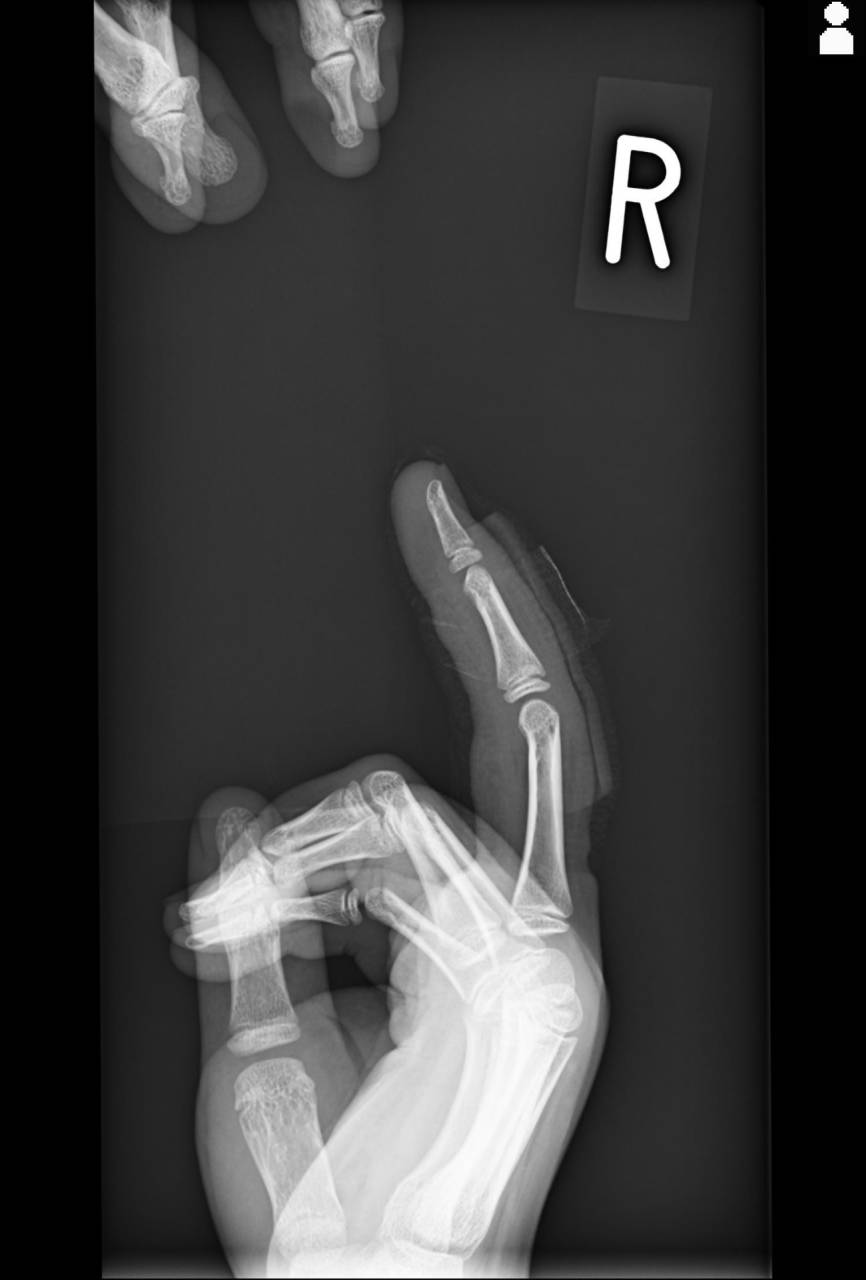

こんにちは、大田区東糀谷の大鳥居駅東口より徒歩2分の場所にある髙山整骨院の髙山です。今回は以前腓骨骨折の方の初回対応と施術について紹介していきましたが、受傷から2ヵ月までの状況を紹介していき…

外部からの強い衝撃を受けたことによる捻挫や継続的なダメージによる骨折、スポーツ時の肉離れなど、様々な怪我の処置やリハビリをサポートしております。身体の健康状態や治り具合などに注意を払いながら痛みの緩和を目指します。なお、より適切かつ迅速に検査や施術を進められるように、エコーや微弱電流などを用いた機器も積極的に使用しております。一人ひとりのお悩みに寄り添い、整骨院ならではの施術を大田区でご案内しております。